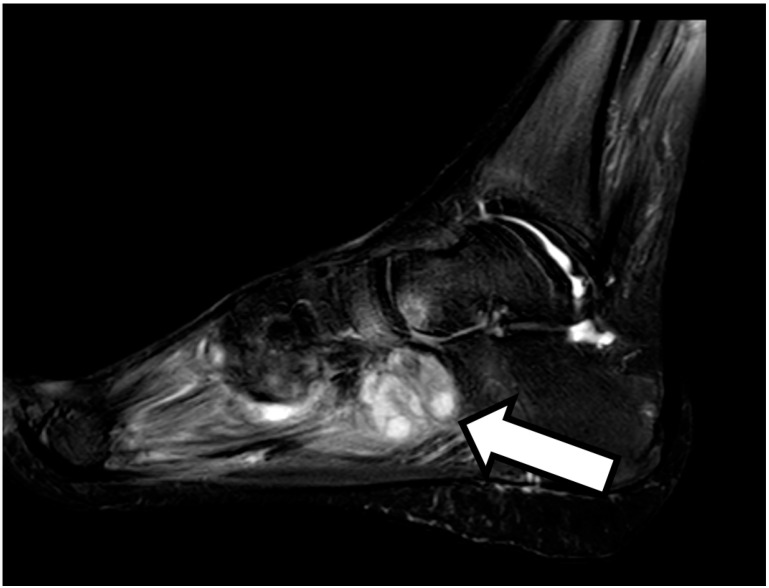

Background: The appearance of new clinical manifestations (for example, subcutaneous or skin abscesses) during anti-tuberculosis treatment is generally indicative of therapeutic failure. The cause of therapeutic failure may be the presence of a drug-resistant Mycobacterium infection or to the failure to achieve a sufficient concentration of the drugs in the bloodstream. Case report: Here, we report the case of a 25-year-old man suffering from tuberculosis infection with lymph-node and pulmonary involvement and an atypical response to specific therapy. Two weeks after starting four-drug antitubercular treatment, the patient began to experience fever, pain and functional impotence in the left foot and ankle, with subsequent evidence of ankle and tarsal osteomyelitis. Four weeks after starting treatment, the patient presented with several widespread, painful subcutaneous abscesses on the trunk, back and right lower limb. Drainage was performed from the ankle and from one of the abscesses, and polymerase chain reaction (PCR) showed a positive result for M. tuberculosis in both samples, with the absence of resistance to drugs. Anti-tubercular medications were continued, with resolution of the pulmonary and bone involvement but with persistence of subcutaneous abscesses, although subsequent drainages showed the absence of mycobacterium tuberculosis. Conclusions: We describe an unusual presentation of paradoxical reaction in the form of osteomyelitis and subcutaneous abscesses in an immunocompetent TB patient, and we reported other similar cases of paradoxical reactions described in the literature in the last ten years, which demonstrate the importance of considering paradoxical reactions in patients who present with new or worsening signs and symptoms after starting tuberculosis treatment.